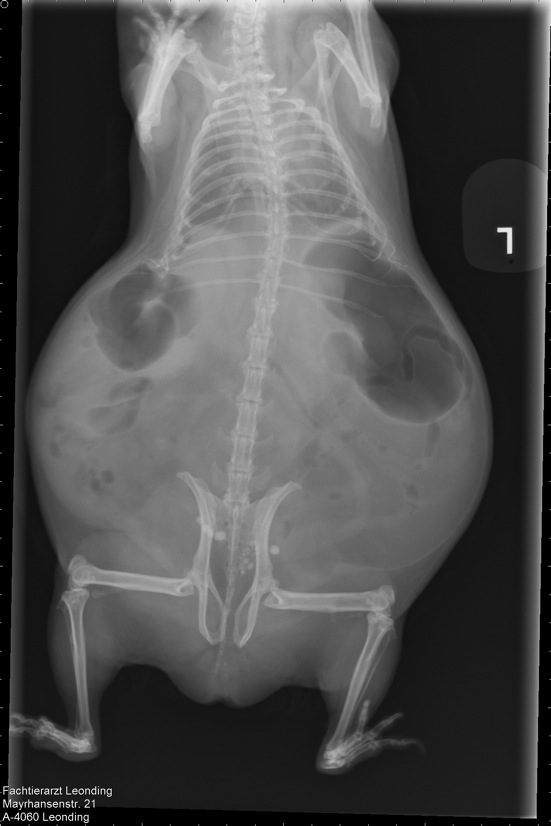

Slika 4,5 godina stare zamorčice Dixie, sa dijagnosticiranim kamencima u mjehuru, popraćenim plinovima u probavi, jer je zamorčica odbila hranu:

Terapija: Sab Simplex i ručno prihranjivanje zbog probave i razbijanja zraka. Metacam zbog bolova, 3 dana po 1 kap, zatim pauza, jer Metacam ide na bubrege. Probiotik, Pro Pre Bac, zatim kašica od kakice zdravog zamorčića.

Nakon tjedan dana, započeta terapija antibiotikom, Enrofloxacin, 0,1ml na dan

Popraćena terapijom za razbijanje kamenaca, Lysium™, 300 mg Tablete, 2 tablete na dan.

Čajevi od crnog sljeza za oporavak sluznice u crijevima i mjehuru, čaj od koprive, čaj od komorača i anisa kao baza za kašice.

Novalgin kapi 500mg/ml, 1-2 kapi na dan, po potrebi, za olakšavanje boli.

Dixie i dalje odbija sama jesti. Zadržava se u toploj vreći koja je postavljena na stalno zagrijavani Snuggle Safe jastučić. Očito ima temperaturu, pa joj toplina odgovara. Odvojena je ogradicom od ostalih zamorčića, kako bi bila pod kontrolom.